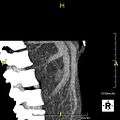

-

Maximum intensity projection (MIP) CT image as viewed anteriorly showing the anomalous hepatic veins coursing on the anterior surface of the liver

Lateral MIP view in the same patient